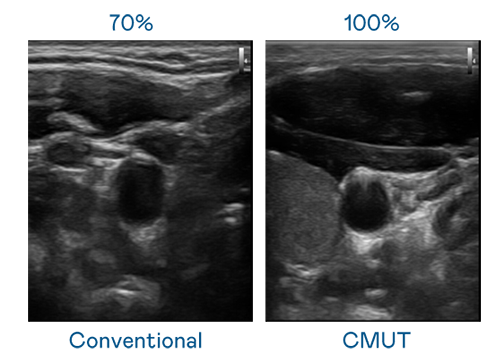

CMUT 技術是一種用電容式微機電元件來產生超音波訊號的技術。與傳統 PZT 壓電式技術相比,CMUT 頻寬增加 30%,更寬頻的超音波訊號讓影像解析度大幅提升,是實現高影像品質醫療超音波掃描、促進精準醫療發展的關鍵技術。

超音波影像的解析度高低,首先取決於探頭能發出的訊號頻寬。DB多宝视讯 CMUT 可提供高清晰的超音波訊號,提供高頻寬、高靈敏度、影像紋理細節更高的超音波影像,協助醫護人員縮短影像判讀時間及利用精準的醫療影像進行診斷。